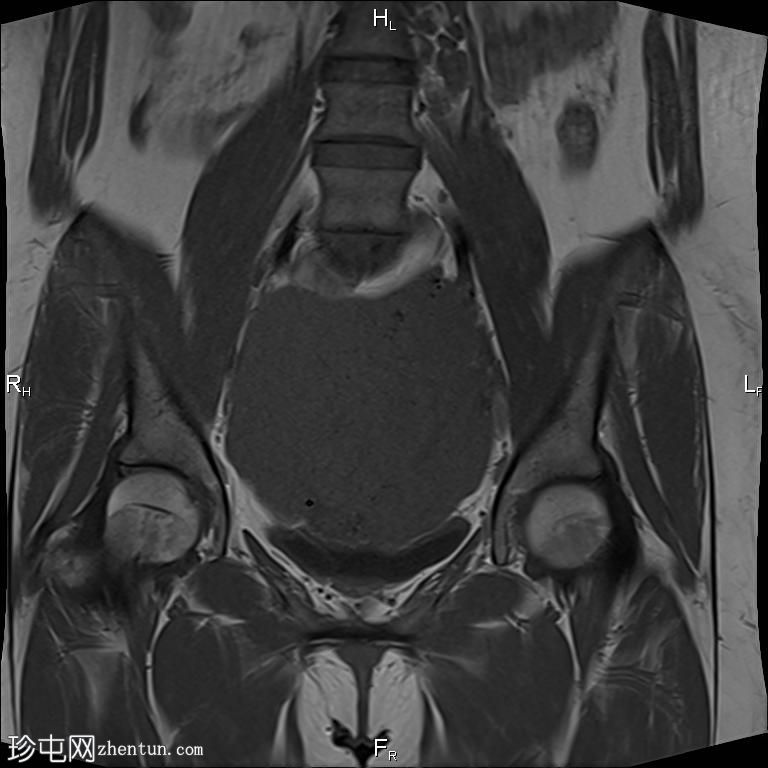

轴向T2

脂肪饱和度

盆腔内可见一巨大多分叶实性肿块,内部有隔膜,T2WI信号不均匀,T1WI信号不均匀,呈低信号。肿块内散在分布囊性/坏死性病变。

肿块外可见子宫和右侧卵巢,肿块似源自左侧卵巢。该肿块压迫膀胱和两侧远端输尿管,并导致肠管和血管结构移位,但无侵袭或包裹征象。

造影后,肿块呈不均匀强化,隔膜强化。

远端髂腹旁和两侧髂骨旁区域可见少量肿大淋巴结。